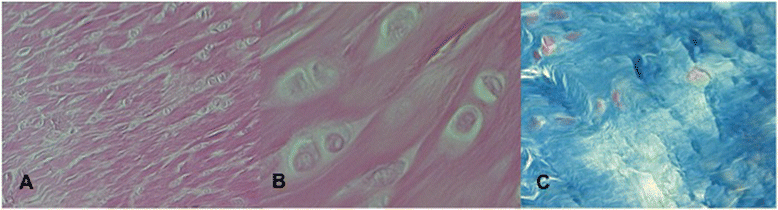

摘要:前交叉韧带(ACL)损伤是膝关节最常见的损伤之一。肌腱可以作为ACL修复的替代移植。本研究的目的是评估在幼兔前交叉韧带重建中半腱肌(ST)发生的形态及组织学变化。材料与方法:21只,8周龄新西兰兔,体重约1500克接受右膝重建手术。在两种情况下,左膝被用来验证兔前交叉韧带ACL和st的正常显微结构。将家兔随机分为七组,分别于术后1, 4, 6、8, 12, 24、48周处死动物。光镜下评估样品来分析移植物关节腔内的变化。对坏死、新生血管和胶原纤维的组织结构进行了研究。结果:术后1个月,发现大量纤维细胞和紊乱胶原纤维。在新韧带愈合的早期阶段,细胞坏死明显减少。4周后,梭形细胞变得更圆。8周后,胶原纤维与新形成的毛细血管和高度分化的成纤维细胞平行排列。移植后24周和48周肌腱和韧带组织学不同。结论:本研究的数据表明,至少术后24个月没有发生韧带化。在愈合过程中,移植肌腱呈现一种独特的微结构,即肌腱和韧带之间的中间结构。近几年来,儿童期ACL重建越来越频繁。远端固定保存半腱肌移植使用应该成为骨骼未成熟患者的金标准。关键词:未成年动物模型 前交叉韧带 韧带化 关节内腔 半腱肌腱背景:前交叉韧带(ACL)在骨骼未成熟的运动员受伤的报道中频率不断增加,占膝关节损伤的31%。青少年ACL重建仍在讨论中。由于骨骺损伤的风险原因,非手术治疗是一个有吸引力的选项。然而,最近的文献一致表明,保守治疗ACL撕裂的儿童导致更高的不稳定率,可能会进展到关节内损伤,包括半月板撕裂。开展早期的手术治疗来恢复未成熟的膝盖骨稳定。尽管肌腱与韧带相比具有不同的生物学和组织学特征,许多研究报道修复韧带肌腱的应用。其中一个仍有争议的问题是澄清这种所谓的"新纽带"如何真的逐渐失去其肌腱韧带组织学特性并表现出特定的生物学特性。虽然已经有大量的研究探索成人ACL重建的各个方面。但关于人类或动物的骨骼未成熟患者肌腱愈合过程的数据很少。一些动物研究表明植入肌腱的确似乎重塑为韧带ACL结构。儿童前交叉韧带重建需要保留骨骺。外科手术应尊重前交叉韧带重建的生物学和生物力学,尽量减少对下肢生长影响的可能性。已经提出了不同的肌腱骨骼未发育成熟的患者手术前交叉韧带重建,但最常用的是半腱肌。本研究的目的是评估重建兔的前交叉韧带,保持其远端插入,一个半腱肌腱关节腔道发生的形态学和组织学的变化。这项研究是对生长的动物进行的,以确定病变的类型和程度。未成熟的动物有更大的组织再生潜能。方法:本实验研究是对用于前交叉韧带重建幼兔模型组织半腱肌超微结构变化的定性描述。该实验得到了当地伦理委员会的批准,并遵循了我们机构的动物护理和使用指南。术前给药动物接受抗生素阿莫西林(10mg/kg),在72小时的时间间隔给予其他两次额外给药,术后2天连续30 mg酮咯酸镇痛治疗。所有健康家兔均进入研究。排除标准为跛行、疼痛或其他疾病体征如化脓性关节炎。对21只新西兰白兔,体重约1500±200 g,右膝进行手术,左膝被用来比较。动物用地西泮(3至5mg/kg)和氯胺酮(500 mg/kg)麻醉。通过内侧髌旁切口,暴露右膝关节。ACL被准确地移除,原始的脚印用无菌铅笔标出。斜2毫米直径的隧道钻,在胫骨中侧和股骨背侧穿过韧带的最初附着物通过生长板。半腱肌腱被切断,在其近端肌肉肌腱交界处,但左健在其远端附着点。肌腱穿过胫骨和股骨隧道,然后用2号丝线缝合在损伤的股骨干骺端外侧的骨膜。手术后用石膏固定七天。尽一切努力减少痛苦,避免负重。手术后,动物们回到了自己的笼子里,自由采食和饮水。动物随机分为七组,每组三只,分别于术后1, 4, 6、8, 12, 24、48周处死。解剖每只动物右后肢,用卡尺和射线照相检测畸形、肢体不等长。左膝用作比较ACL的正常超微结构。实验组和对照组标本用10%福尔马林固定。后使用EDTA进行脱钙、石蜡包埋。5μm厚切片用H&E染色,马松三色染色、Alcian-PAS等染色。光镜下评估样品来分析移植物关节腔内的变化。所有标本均与正常兔前交叉韧带结构进行比较。结果:在整个研究期间都观察了与动物有关的任何并发症。所有的移植物在评估时都完好无损,没有正常ACL的珍珠状外观。动物在死亡时没有观察到失败的半腱肌移植。术后1周,移植组织显示灶性无细胞区坏死。术后3-4周时能更好的评价组织坏死,如强烈的炎症反应。但手术后40天内就不再检测到了。术后1个月出现大量成纤维细胞,可见大量胶原纤维排列紊乱。纤维状的胶原蛋白,如I和III型,提供肌腱和韧带的基本构件,具有弹性和强度。成纤维细胞初始纵向布置在肌腱的中心位置。血管仍然很差,血管位于移植物周围。在半腱肌腱,成纤维细胞呈梭形,与前交叉韧带成纤维细胞不同。然而,4周后,这些梭形细胞变得更圆。第一个月后胶原纤维排列紊乱,胶原纤维变得更有组织性。术后第四~第八周,典型炎性细胞逐渐消失。坏死区未检出。术后8周时,胶原纤维平行排列与新生的毛细血管和成了高度分化的成纤维细胞。半腱肌腱,移植后最初没有血管,逐渐成为血管,特别是术后40天。然而,在这个时间点移植,没有出现类似于ACL。与正常左膝韧带相比,手术膝关节的平均移植物截面积显著增高。在新韧带(24周)愈合过程中,随着胶原纤维直径的改变,正常胶原方向和卷曲模式消失,从大到小,I型胶原纤维的减少和Ⅲ型胶原合成的增加。24周后处死动物的组织学特征在48周内无进一步变化。在24到48周之间,移植物尚未获得正常的兔ACL在关节腔内的特征。结论:未成年兔术后长达48周的时间没有形成韧带化过程。移植的ST在愈合过程中变成一个新的实体,在肌腱和韧带之间有一个微结构。半腱肌移植经历了一个适应的过程,而不是完全恢复完整的ACL的生物学特性。